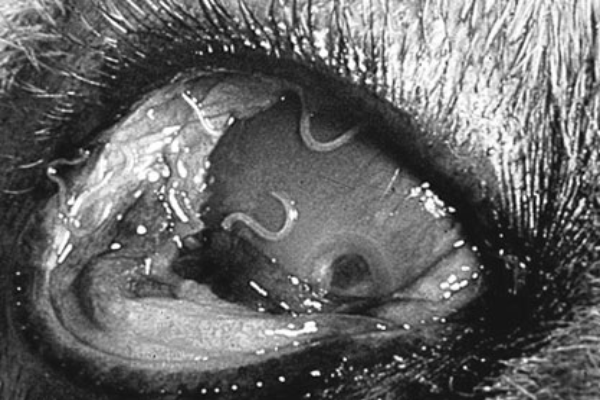

Телязиоз (thelasiosis) – зоонозное нематодозное заболевание, вызываемое нематодами телязиями, паразитирующими в протоках слезных желез, конъюнктивальном мешке и под третьим веком; с признаками конъюнктивита, слезотечения, помутнения и изъязвления роговицы, сопровождающееся угнетением, снижением продуктивности животных, нередко потерей зрения.

Телязиоз крупного рогатого скота возникает при заражении нематодами семейства Thelaziidae: • Т. rhodcsi — поражают конъюнктивальный мешок, область третьего века; • Т. gulosa и Т. skrjabini — поражают слезно-носовой канал, слезные железы; Телязии имеют червевидную форму и достигают 20 мм в длину. Гельминты желтовато-серого цвета; различаются по строению кутикулы, величине ротовой капсулы, строению спикул у самцов. Их развитие отличается сложным циклом и предполагает наличие промежуточных хозяев. Ими выступают мухи-коровницы.

У инвазированных животных начинается слезотечение, конъюнктивиты, отек век и светобоязнь. Отмечается гиперемия слизистых оболочек глаза и повышенная их чувствительность. Роговица мутнеет и приобретает желто-красный оттенок. Процесс может сопровождаться изъязвлением роговицы, выпячиванием глазного яблока и в конечном итоге полной слепотой. Чаще поражается один глаз. Длительность болезни зависит от глубины наступивших патологических изменений и колеблется от нескольких дней до 2 месяцев. Особенно тяжело протекает телязиоз у молодняка, впервые инвазированного телязиями. Повторное заболевание протекает легче.

Личиночные и молодые формы телязий оказывают механическое воздействие на конъюнктиву и роговицу, что сопровождается внедрением патологической микрофлоры и развитием конъюнктивита серозного или гнойного характера. Поврежденная роговица мутнеет, а воспаленная конъюнктива настолько сильно опухает, что веки полностью закрывают больной глаз. На роговице образуются эрозии. С развитием воспалительных процессов в помутневшей роговице формируется язва круглой или овальной формы и глазное яблоко сильно выпячивается. С течением времени роговица постепенно заживает, диффузное помутнение рассасывается и глаз приобретает нормальный вид. На месте бывшей язвы, как правило, остается белое пятно различной величины.